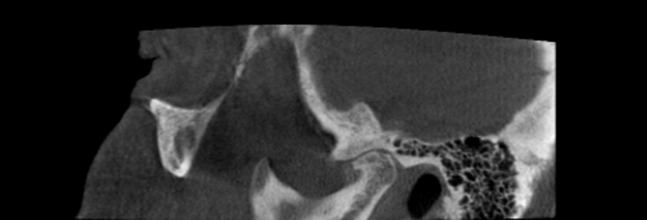

Pneumatization of the temporal bone may be a diagnostic challenge for the assessment of cortical erosions in the articular eminence if they reach the articular surface, and CBCT is the superior method to depict such anatomic variations.97

CBCT has been applied in the evaluation of bifid mandibular condyles,98,99 coronoid hyperplasia100 and articular eminence morphology101–103 and to assess condylar remodelling accompanying splint therapy.104